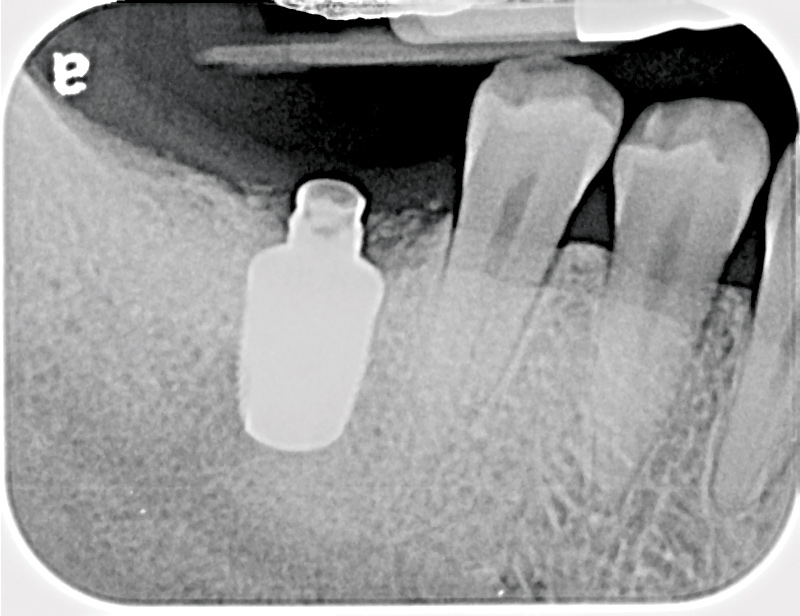

Fig 6. Radiograph following crown fracture.

Figure 6